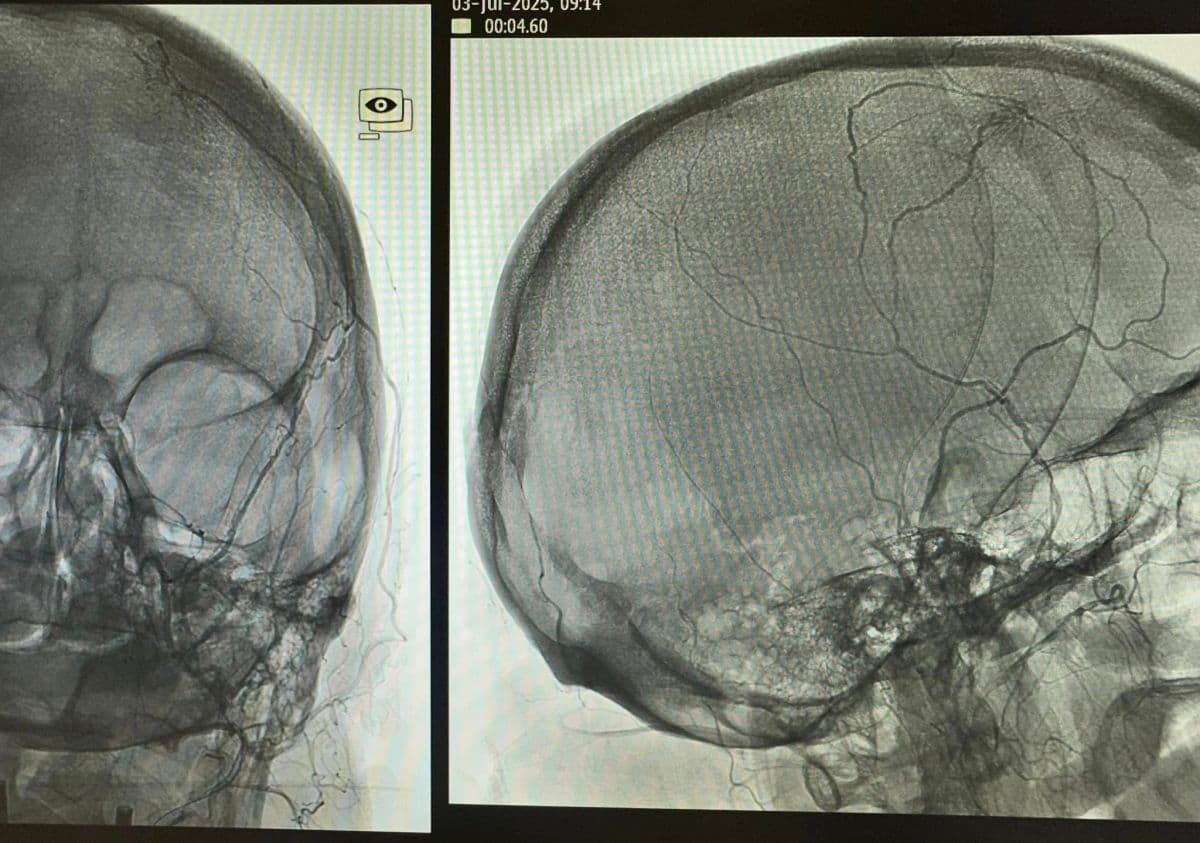

Presurgical Embolization of Brain Meningiomas reduces intraoperative hemorrhagic events and fascilitates surgical excision (Professor of Neurosurgery and Endovascular Neurosurgery V. Panagiotopoulos & Professor of Interventional Neuroradiology P. Zampakis).